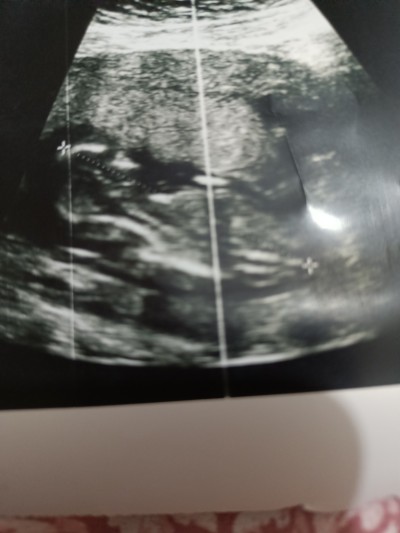

kizlar 14 haftalık cinsiyet ne olabilir sizce

Belli olmuyor ama kemik yapısı erkeğe benziyor

Kız geçti içimden canım sağlıkla kavuşun inşallah

Kizada benziyor erkeğe de ama sanki kız gibi

Kız gibi bence de

Çünkü erkekte testis var ama testisler böyle görünmüyor kız böyle görünüyor

bu şekilde benimki erkek böyle gördük

Kız gibi geldi bana